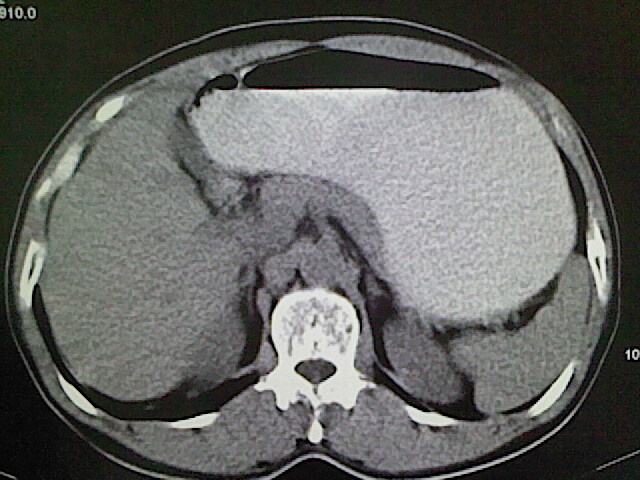

标题: CT18630:男,54岁,乙肝,大家看怎么样? [打印本页]

男,54岁,乙肝,大家看怎么样?

肝脏的要有增强敢说话

未见明确异常;建议必要时行ct增强扫描检查。